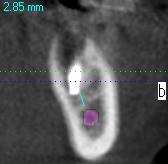

術後のCTになります

安全も確認して埋入しています

4mmの13mmというインプラントを埋入しています